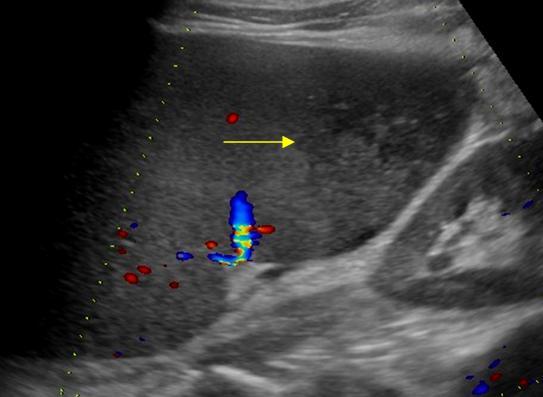

Nhồi máu lách

» Thông tin: Nam giới – 74 tuổi.

» Lâm sàng: Đau mạn sườn trái.